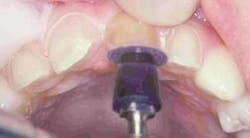

Preparation of the four incisors was then initiated using diamond burs from the Shofu Contemporary Cutting Kit (Figure 5). With the high-speed ElectroTorque KaVo handpiece, a small round diamond (0872-1) was used to outline the peripheral margins of the preparations (Figure 6). By scoring the facial surface of the incisors with the depth cutter (0897-1) (Figure 7), smooth and uniform tooth structure removal using a coarse tapered diamond (0835C-1) was facilitated (Figure 8). As tooth nos. 9 and 10 were prepared, it came time to address the gingival contour issues of the inflamed interproximal gingiva.